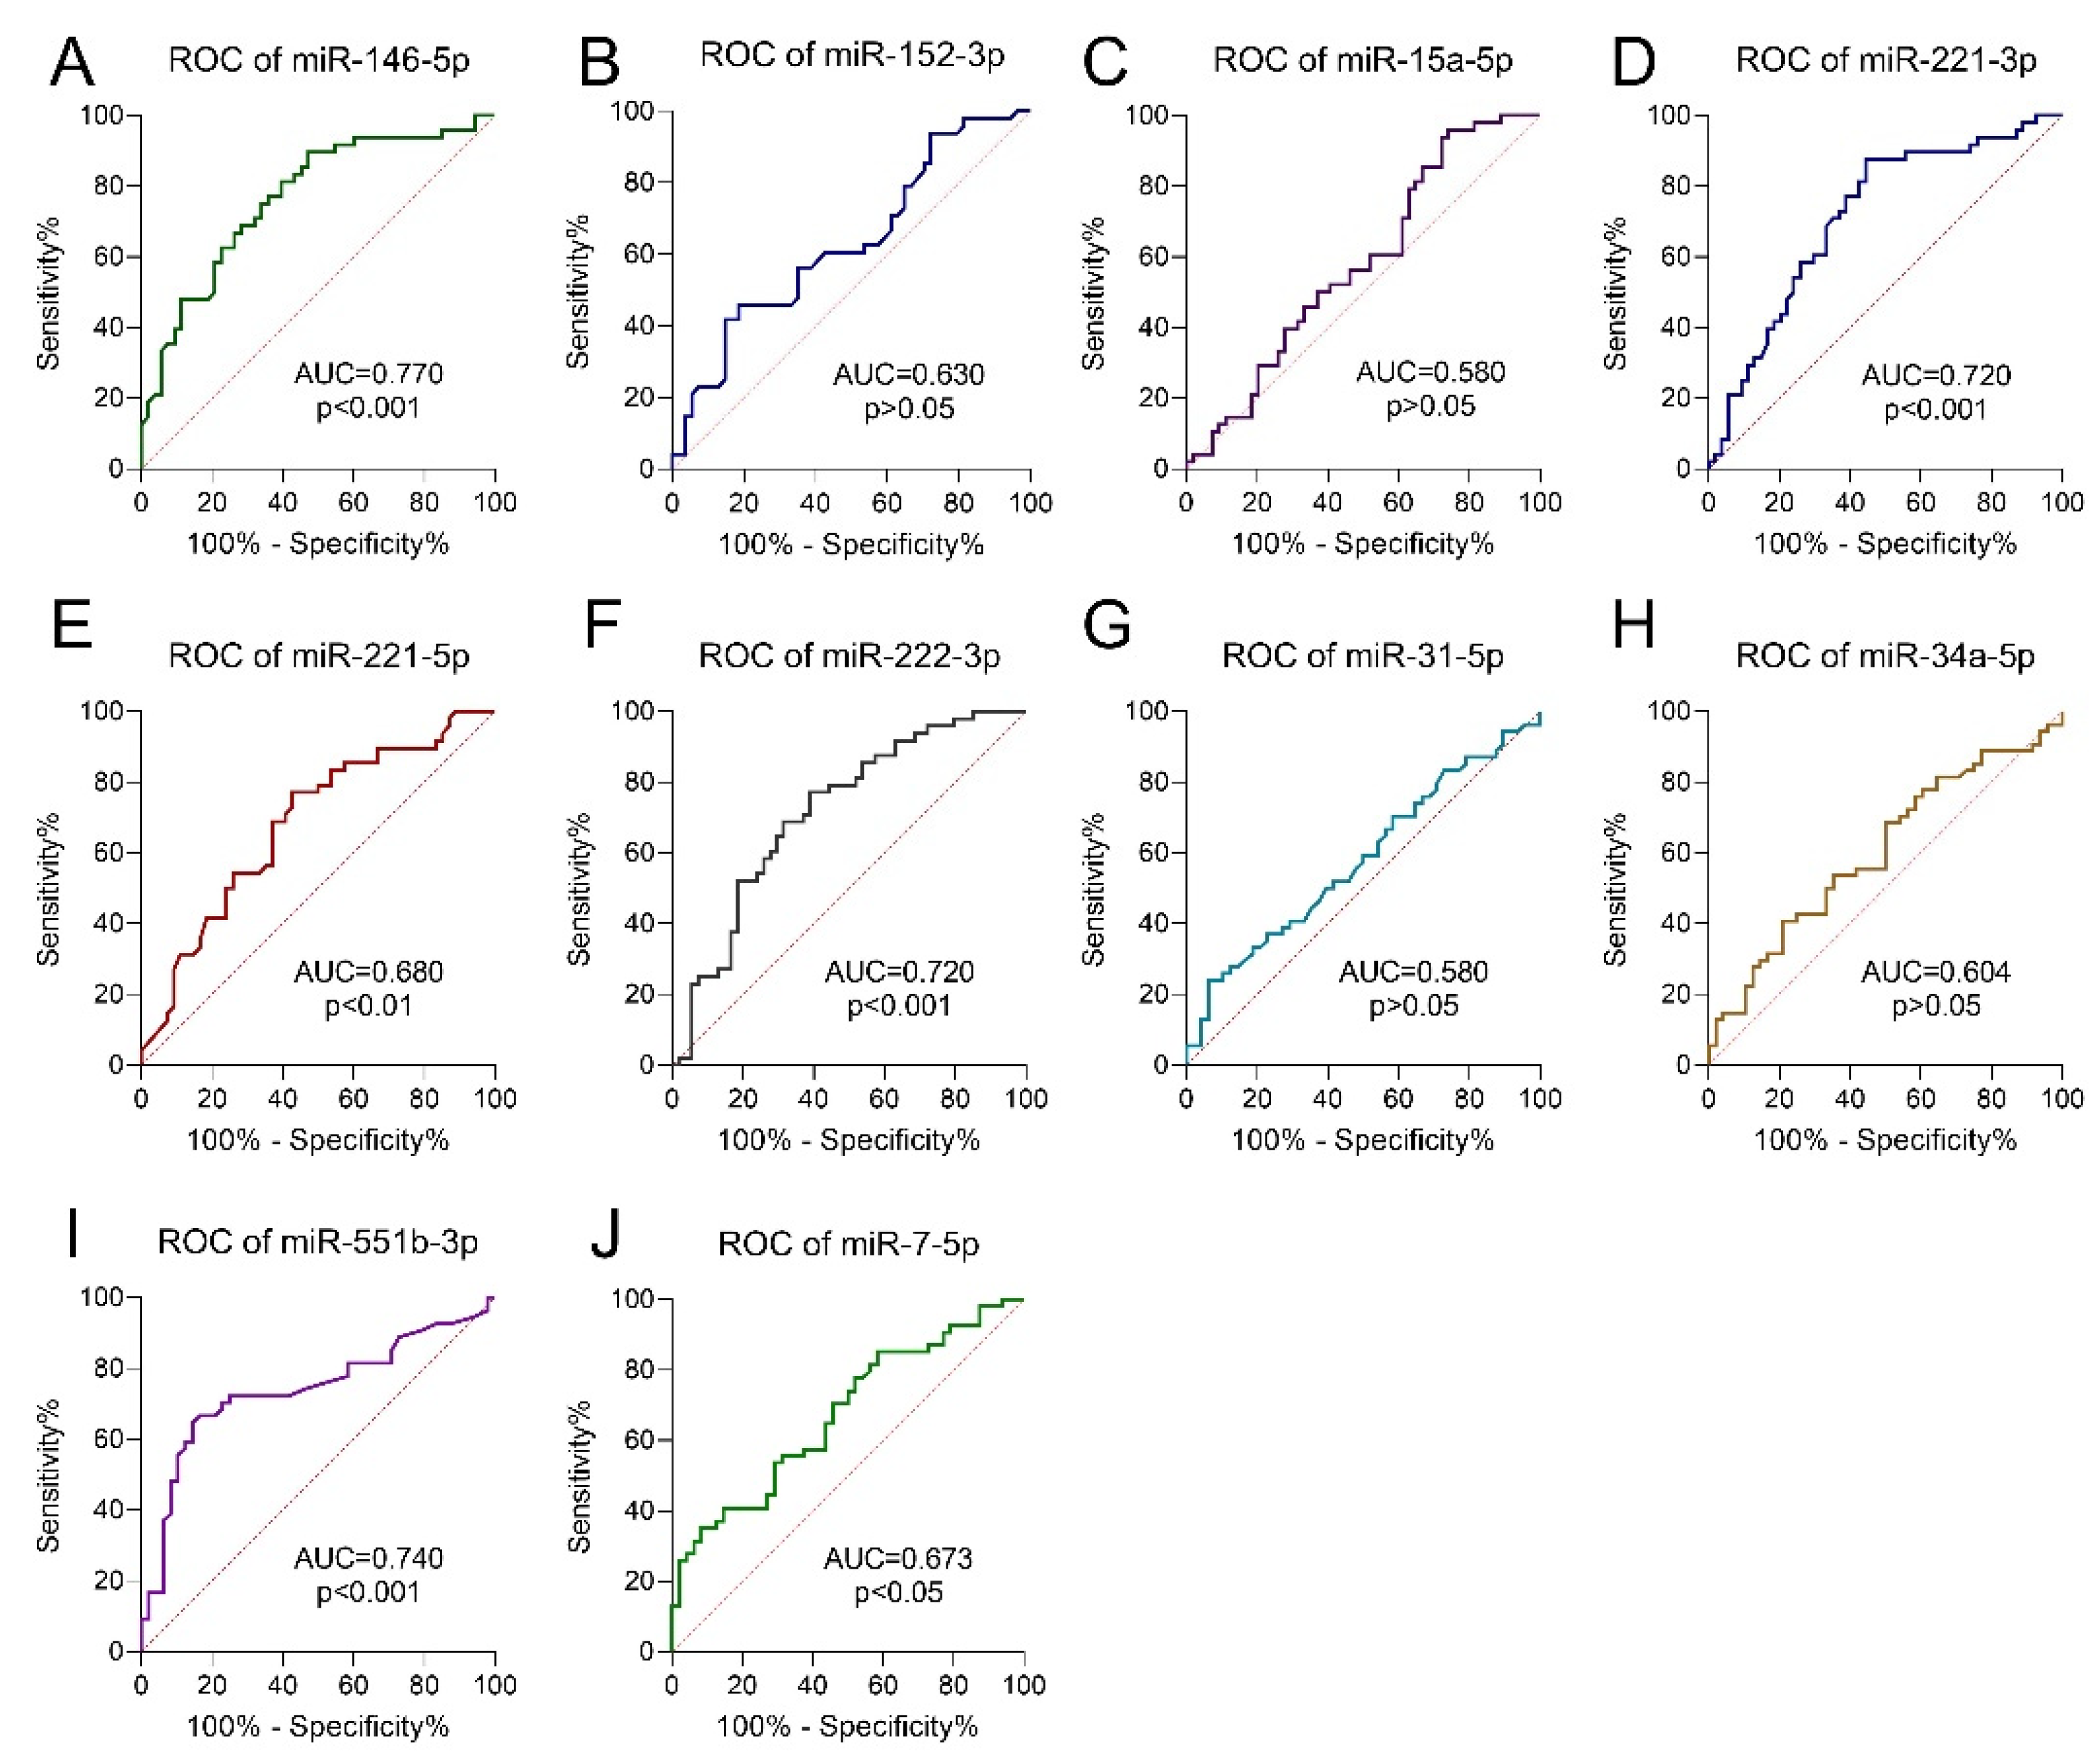

3.5. Receiver Operating Characteristic Curve Analysis

| miRNA | FC | p-Value | FDR |

|---|---|---|---|

| miR-146b-5p | 6.62 | 0.00000001 | 0.00 |

| miR-221-3p | 3.23 | 0.00000001 | 0.00 |

| miR-221-5p | 2.36 | 0.00000016 | 0.00 |

| miR-222-3p | 2.94 | 0.00000001 | 0.00 |

| miR-34a-5p | 1.65 | 0.00002568 | 0.00 |

| miR-551b-3p | 2.63 | 0.00000003 | 0.00 |

| miR-152-3p | −1.53 | 0.00040006 | 0.01 |

| miR-15a-5p | 1.57 | 0.00031352 | 0.01 |

| miR-31-5p | 1.60 | 0.00051338 | 0.02 |

| miR-7-5p | −2.57 | 0.00108612 | 0.03 |